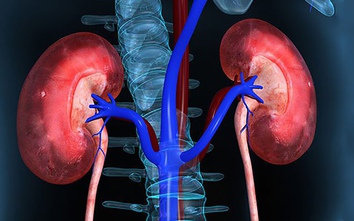

7 loại trái cây tốt cho thận, người bệnh suy thận nên ăn để duy trì chức năng thận

GĐXH - Việc lựa chọn hoa quả phù hợp, ít kali và ăn đúng lượng khuyến nghị sẽ giúp hỗ trợ chức năng thận và hạn chế nguy cơ biến chứng ở người bệnh suy thận.

6 loại rau người bệnh suy thận nên ăn để giảm gánh nặng cho thận

GĐXH - Theo các chuyên gia, nếu biết lựa chọn và chế biến đúng cách, người bệnh suy thận vẫn có thể sử dụng nhiều loại rau xanh an toàn trong bữa ăn hằng ngày.

5 sai lầm khi uống nước có thể gây suy thận, nhiều người Việt vẫn mắc phải

GĐXH - Theo các chuyên gia dinh dưỡng, nhiều người đang mắc phải những sai lầm phổ biến khi uống nước, làm tăng nguy cơ suy thận mà không hề nhận ra.